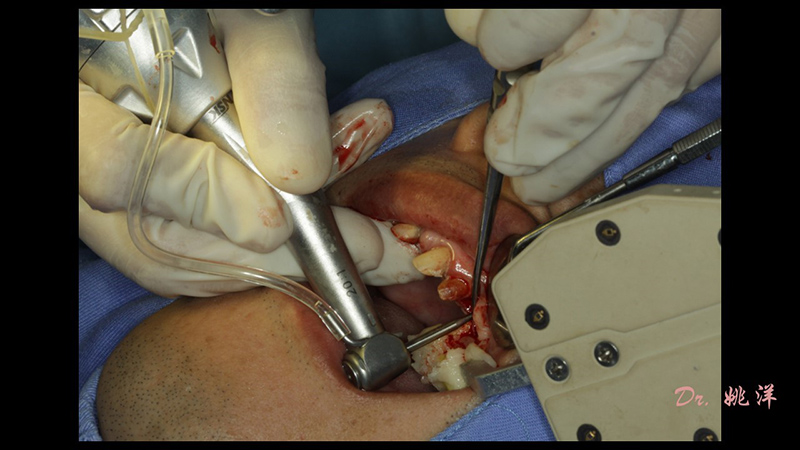

術(shù)中操作

導(dǎo)航下精細(xì)分配修復(fù)間隙,精細(xì)規(guī)劃植入方向,避開(kāi)上頜竇底,精確植入